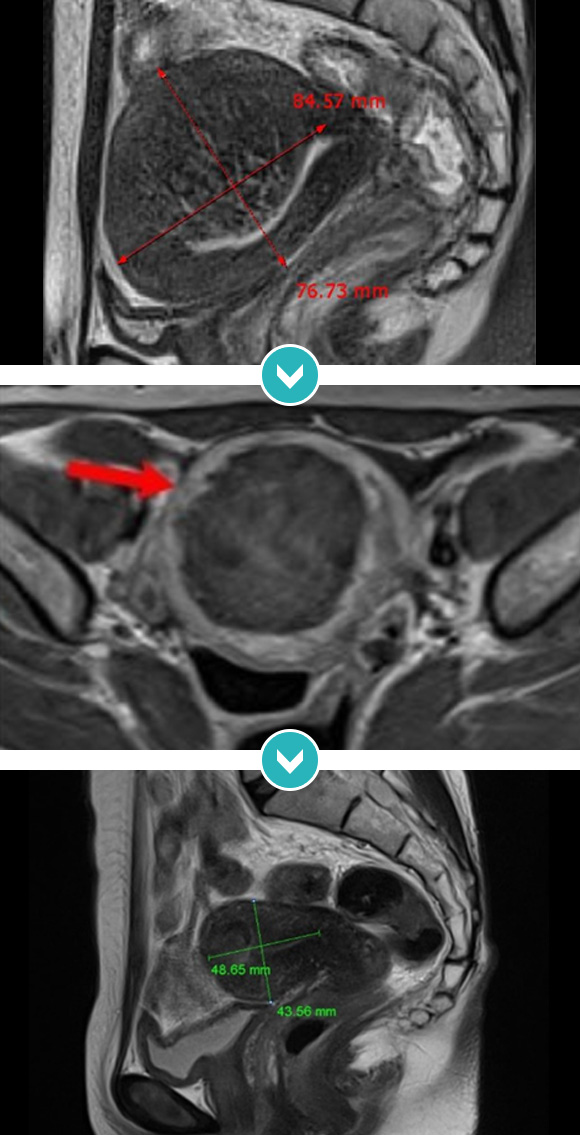

8cm 크기 자궁후벽과 저부 자궁선근증 하이푸 치료후 90%이상 치료, 42개월 장기 추적관찰